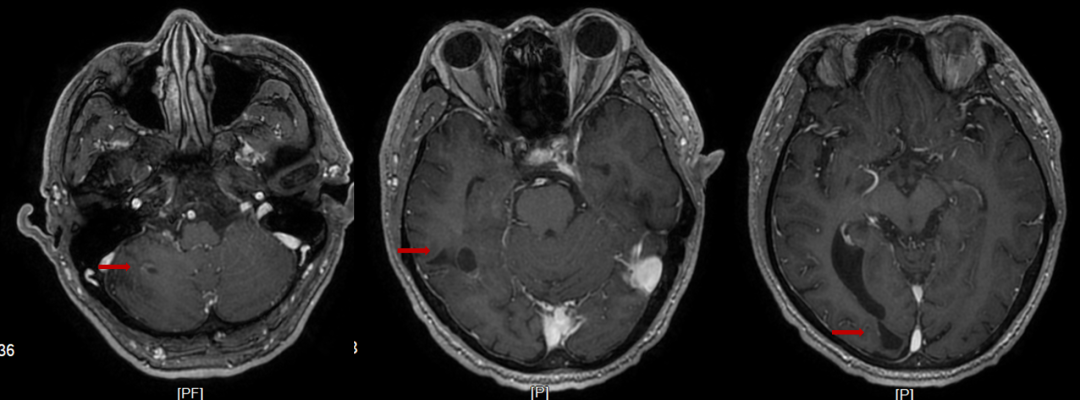

2023年3月21日(维持治疗4周期后)颅脑MRI:右侧小脑半球、右侧颞、枕叶及双侧侧脑室旁、右侧半卵圆中心多发异常信号,对比2023.01.02号片右侧小脑半球、右侧颞叶病灶有减小。

图5.治疗后颅脑MRI

图6.维持治疗后颅脑MRI

该患者就诊时为有症状脑转移患者,依据CSCO指南建议先行全脑放疗,症状稳定后再进行系统治疗。但该患者入院时头痛明显,烦躁,无法配合放疗体位固定,仅能接受紧急药物降颅压治疗,患者头胀痛减轻,但仍有言语不利、肢体活动不利,该患者一线使用斯鲁利单抗联合化疗的治疗方案,症状快速缓解,生活质量明显提高,一周期后水肿带消失。斯鲁利单抗联合化疗治疗3周期后,影像学显示,脑转移灶明显缩小,6周期治疗后脑转灶消失。既往研究显示,少有单纯化疗对脑转移灶产生良好的控制效果,此案例显示了斯鲁利单抗对脑转移患者具有良好的抗肿瘤疗效。ASTRUM-005研究中,纳入12.9%的基线伴脑转移患者,为同类研究中入组脑转移患者比例最多的临床研究,研究结果显示,斯鲁利单抗联合治疗组脑转移患者OS达13.9个月,而对照组仅为10个月,HR 0.61(95%CI 0.33-1.13)[7]